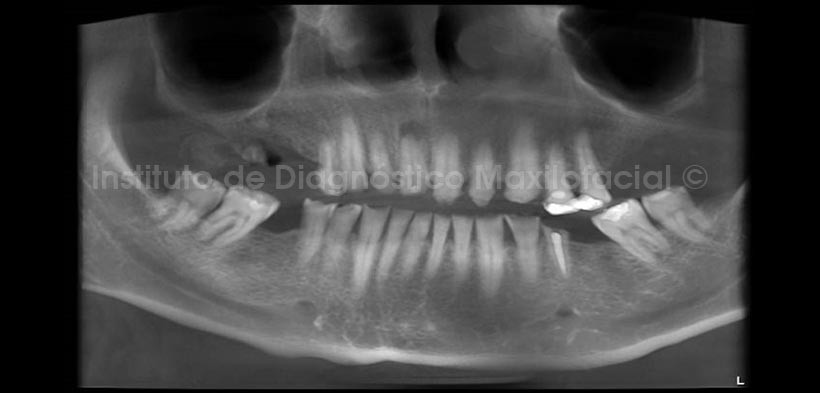

En la evaluación con tomografía volumétrica, en la reconstrucción panorámica (Fig.2) se observa la perdida de estructura dentaria mencionada, así mismo nótese la lesión apical en la pieza 1.1, la misma que en la radiografía panorámica se mostraba discretamente.